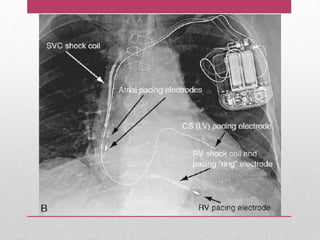

MARCAPASOS - Es ungenerador de impulsos electricos, el cual consta de un circuito integrado que se compone de un microprocesador, varios transistores electrónicos y una batería. - Todos estos componentes están incorporados en una capsula de titanio sellada con laser. TIPOS DE MARCAPASOS TEMPORALES PERMANENTES MONÓ CAMERA BICAMERALES MONÓ CAMERA BICAMERALES TRI - CAMERALES

MARCAPASO Y CARDIO-DESFIBRILADOR( PERMANENTE) MONÓ CAMERA BICAMERALES TIPOS DE ELECTRODO - ESTIMULADOR UNIPOLARES BIPOLARES - Para liberar una descarga eléctrica el sistema generador de pulsos -electrodo, necesita dos electrodos para que la electricidad viaje. UN ELECTRODO ESTA EN EL EXTREMO DISTAL DE LA SONDA DE ESTIMULACIÓN Y EL OTRO ES LA CAJA DEL GENERADOR LOS DOS ELECTRODOS SE ENCUENTRAN EN EL EXTREMO DISTAL DE LA SONDA DE ESTIPULACIÓN Y ESTÁN SEPARADOS POR UNOS CENTÍMETROS